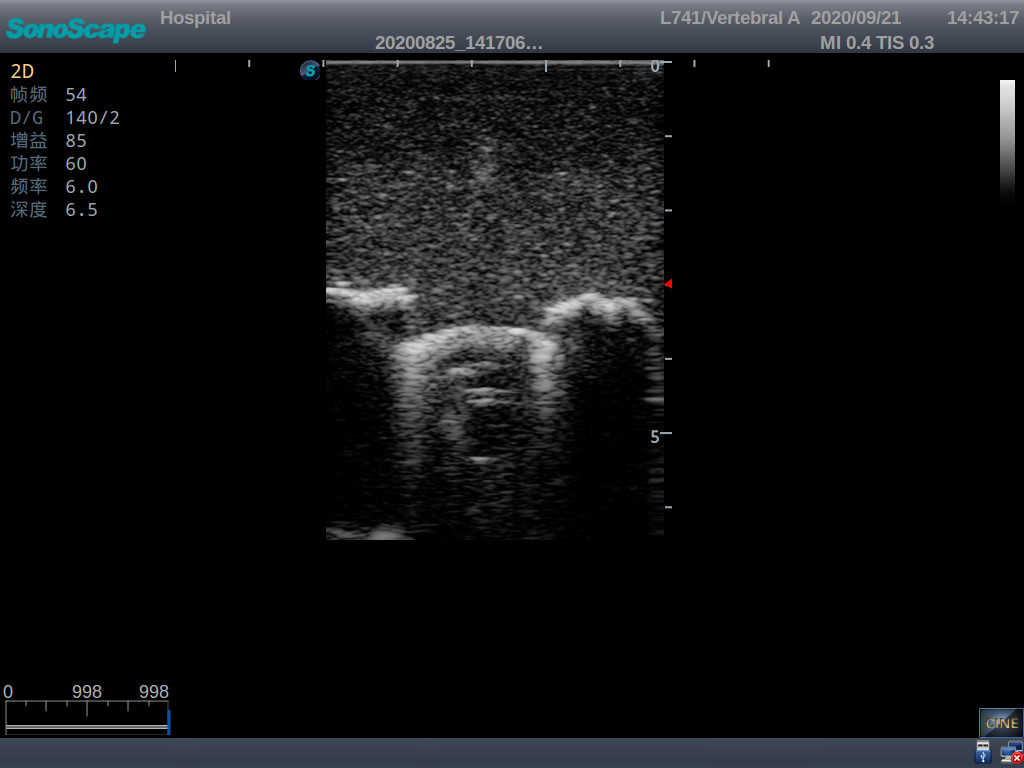

2) Real clinical ultrasound images

3) Compatible with various real ultrasound machines